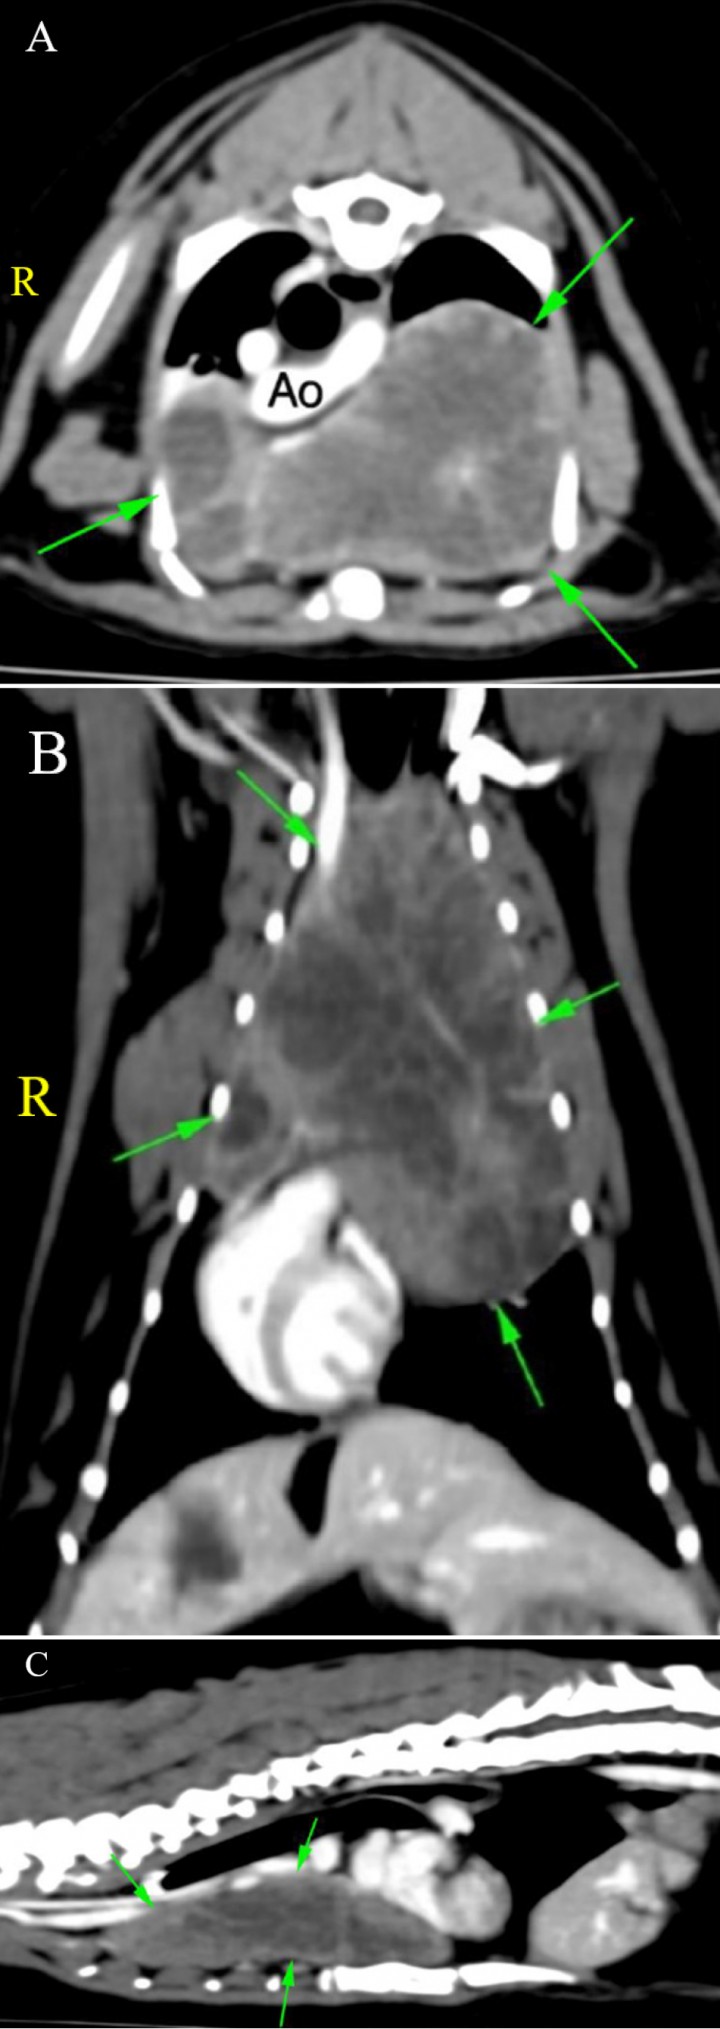

Se realizó TC de tórax y abdomen (Fig. 3). En el tórax se apreció una masa de grandes dimensiones (7,8 x 4 x 5 cm), hipodensa, que mostraba un realce heterogéneo tras la administración de contraste, localizada en el mediastino craneoventral y lateralizada a la izquierda. Esta producía un moderado efecto masa con desplazamiento de la tráquea y los vasos mediastínicos hacia dorsal y a la derecha, así como el corazón hacia caudal y a la derecha. No se observó evidencia de metástasis a nivel torácico ni abdominal.

<p>Imágenes de TC de tórax en ventana tejido blando postcontraste. (<strong>A</strong>) Plano transversal. (<strong>B</strong>) Plano dorsal. (<strong>C</strong>) Plano sagital. Se observa una masa en el mediastino craneoventral de grandes dimensiones (flechas verdes). (R: derecha). Ao: arteria aorta.</p>

Imágenes de TC de tórax en ventana tejido blando postcontraste. (A) Plano transversal. (B) Plano dorsal. (C) Plano sagital. Se observa una masa en el mediastino craneoventral de grandes dimensiones (flechas verdes). (R: derecha). Ao: arteria aorta.